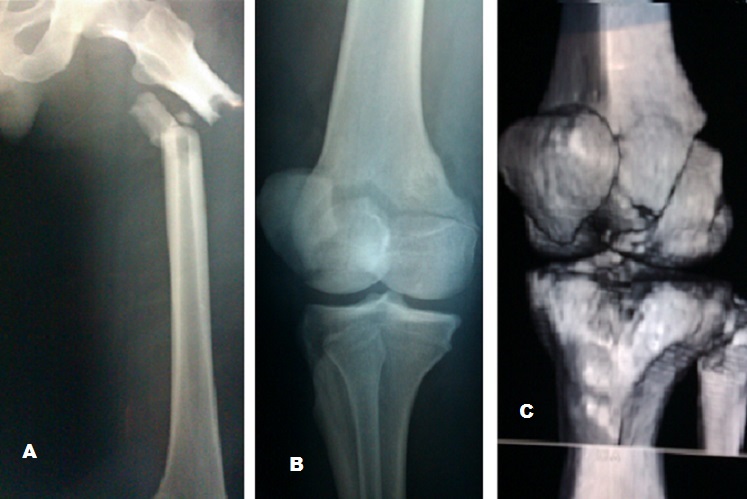

L'association fracture de la diaphyse fémorale et fracture de Hoffa de l'extrémité inférieure du même fémur est très rare, peu de cas sont décrit dans la littérature. Elles surviennent après un traumatisme à haute énergie surtout lors des accidents de la voie publique. Elles touchent par conséquent une population jeune. Notre patient est âgé de 27 ans, il a été victime d'un accident grave en conduisant sa moto. Le diagnostic est évoqué devant l'association d'une déformation de la cuisse et une hémarthrose du genou. L'examen vasculo nerveux doit être systématique par la palpation des pouls distaux et exploration du SPE et SPI. La confirmation diagnostique est faite après un bilan radiologique comprenant une radiographie standard de tout le fémur et des radiographies de face, profil et ¾ du genou éventuellement complétées par une TDM avec reconstruction 3D permettant de mieux visualisé la fracture de Hoffa. Le traitement est chirurgical consistant en enclouage centromédullaire à foyer fermé de la fracture du fémur, associé à un vissage percutané ou à foyer ouvert de la fracture de Hoffa en fonction des possibilités réductionnelles. Le pronostic est dominé par le risque important de raideur du genou. Diagnostic reten: fracture diaphysaire du fémur avec une fracture de hoffa associée 3 diagnostics différentiels: fracture du fémur associé à une rupture du LCP, fracture du fémur associée à une fracture de la rotule, fracture de fémur associée à une rupture du LCA